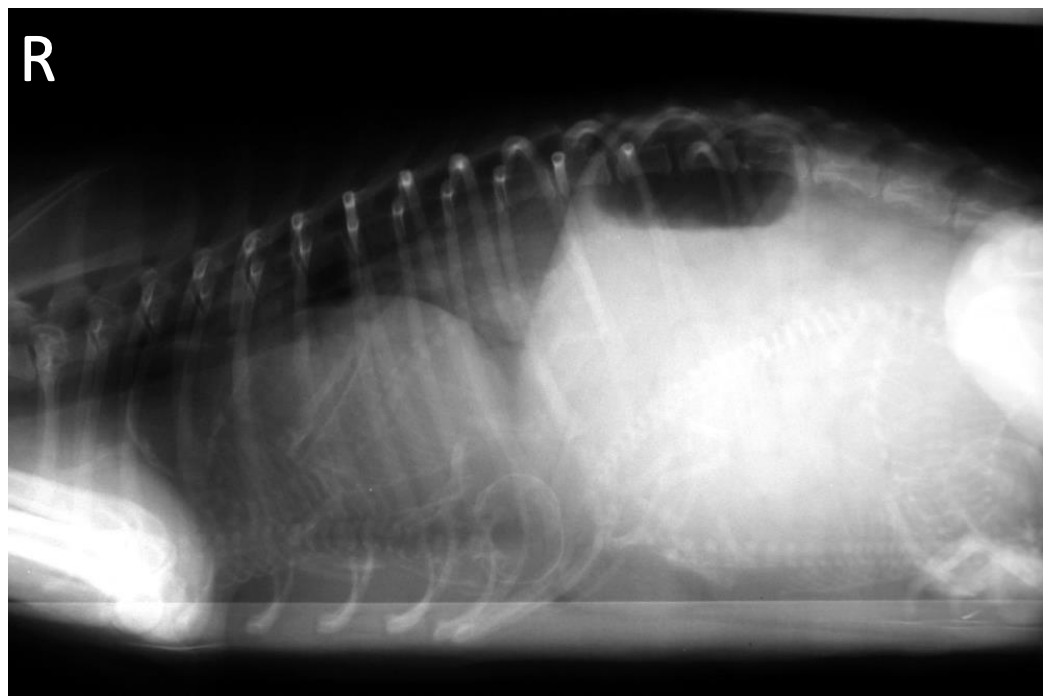

What is shown in this image?

normal non-gravid uterus in an intact female dog